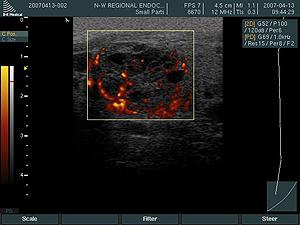

Энергетическая допплерография демонстрирует общее количество движущихся частиц, отражая интенсивность кровотока в исследуемом участке. На энергетическом допплеровском исследовании интенсивность покажется разными оттенками красного — от оранжевого до коричневого. Этот метод используется для уточнения результатов в случае неясности после цветного допплера.

Само кровоснабжение щитовидной железы может быть усилено. Существует термин – thyroid inferno («щитовидный ад»), который описывает резкое увеличение кровотока во всей ткани щитовидной железы. Это проявление чаще всего наблюдается при аутоиммунных заболеваниях, таких как диффузный токсический зоб и иногда при тиреоидите Хашимото.

По наблюдениям, на ранних стадиях опухоли имеют низкую васкуляризацию, которая увеличивается по мере роста образования. Кровоток в щитовидной железе служит индикатором её гормональной активности. При диффузном токсическом зобе, по мере прогрессирования состояния, наблюдается рост кровоснабжения. При наличии выраженных изменений на УЗИ с цветным доплером железа выглядит как пылающее пламя.

На ультразвуковом исследовании представлено изображение диффузно-токсического зоба.